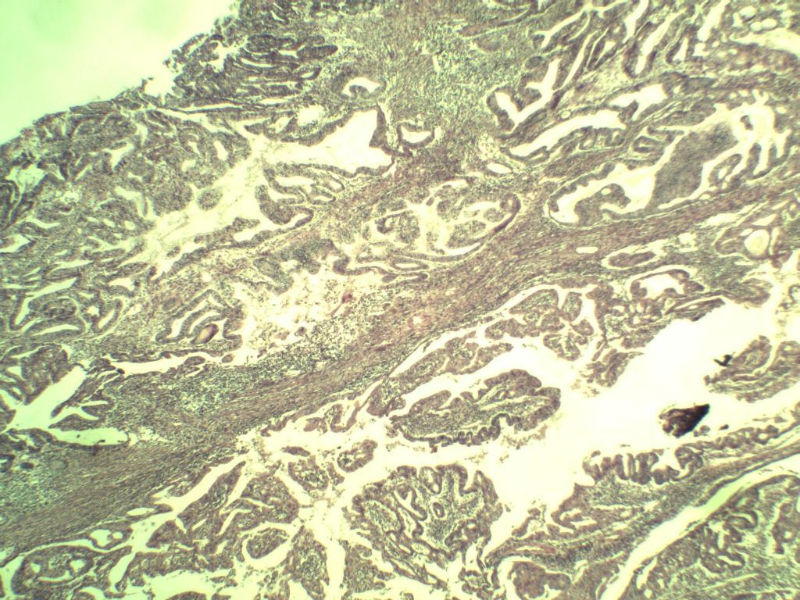

女,57岁,全切子宫一个,宫体体积 9 × 8 × 7 cm3,肌壁厚 2.5 cm,内膜菲薄,部分区域增厚达 0.4 cm(约3*2.5cm区域)。 请问各位老师 这个可以诊断子宫内膜癌了吧? 深肌层没有看到浸润。

患者因"发现下腹部包块1月多"入院 宫体体积 9 × 8 × 7 cm3,肌壁厚 2.5 cm,内膜菲薄,部分区域厚 0.4 cm(约3*2.5cm)。宫颈结构不清,长约 2.5 cm,表面欠光滑。临床诊断宫颈宫腔积液.

名称:图1

描述:a144.Jpg.jpg